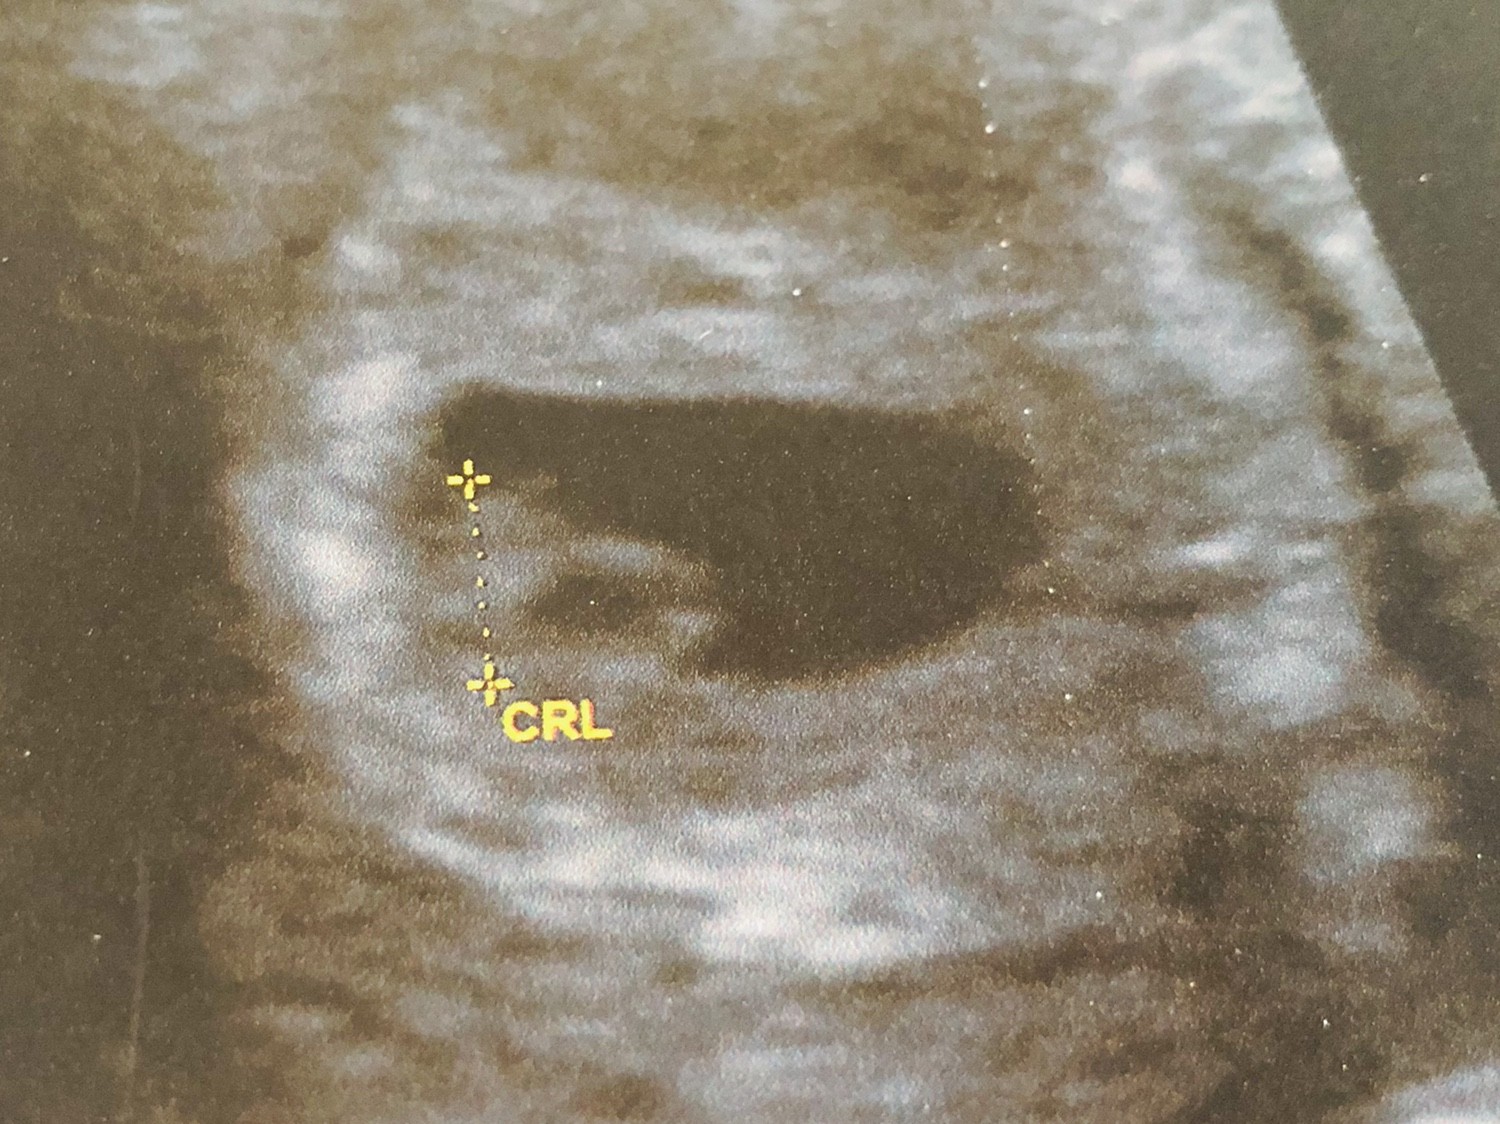

Dzisiaj już po pierwszym skanie :)

Serduszko bije [emoji173]️

Termin idealnie pokrywa się z moimi obliczeniami czyli 10-11/12